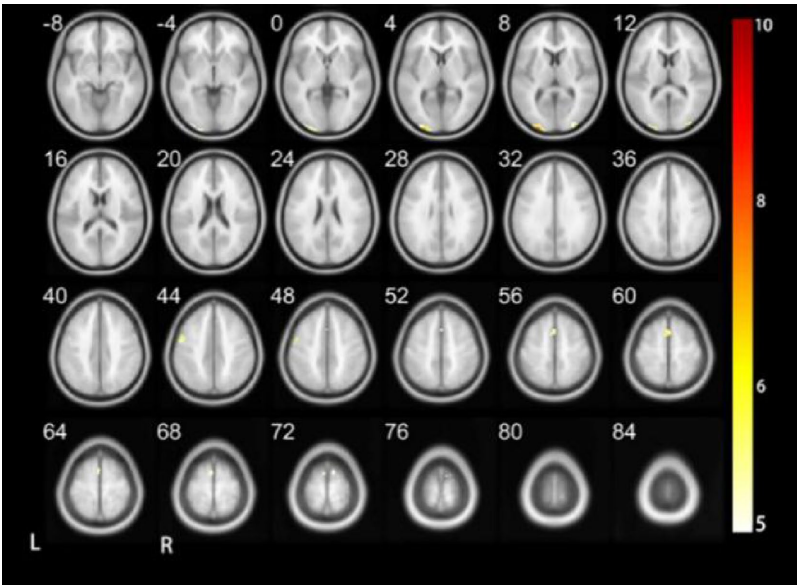

听觉皮层功能缺陷的神经证据

对比正常儿童在音调II任务中活跃的颞中回(听觉语义整合)和顶下小叶(听觉空间注意),聋儿童这些区域均未激活(p<0.001)。这印证了Kral等提出的"听觉皮层功能退化"理论,说明长期听觉剥夺会导致相关脑区功能萎缩。